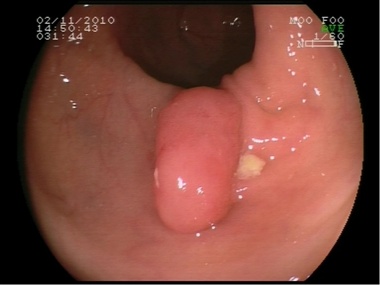

Pólipo